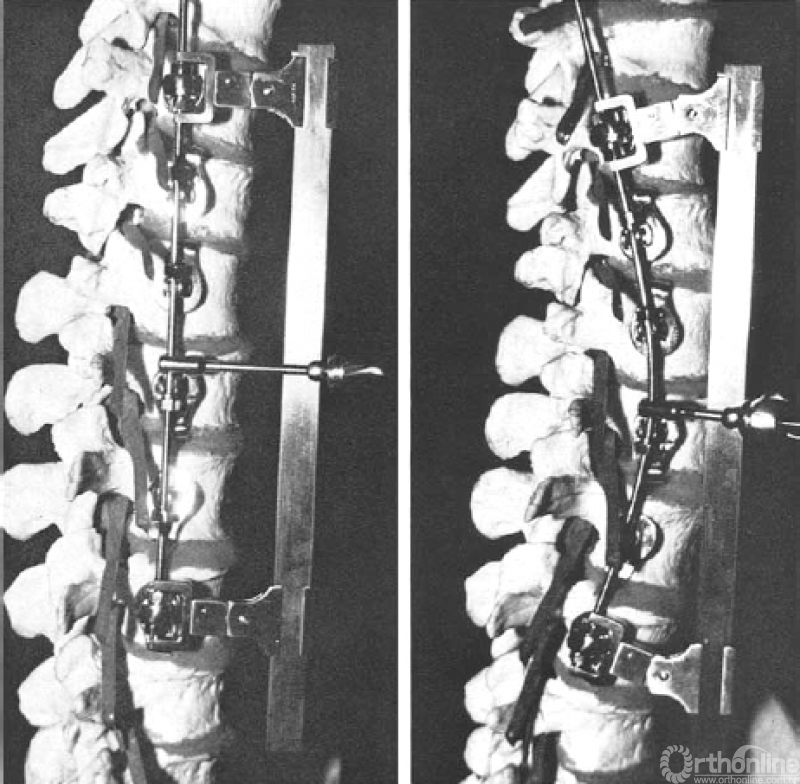

脊柱前路融合内固定技术用于治疗部分类型的青少年特发性脊柱侧凸至今已有五十多年历史。Dwyer等人[1]在1964年首先对其进行了描述。1976年Zielke等人[2]对其进行了改进,用金属棒代替了连接椎体螺钉的线缆,并提出了腹侧去旋转脊柱融合技术(VDS,Ventrale Derotation Spondylodesse),该器械操作有效地矫正了冠状面脊柱侧凸,改善了顶椎去旋转。

图1. 1976年Zielke等人提出腹侧去旋转脊柱融合技术